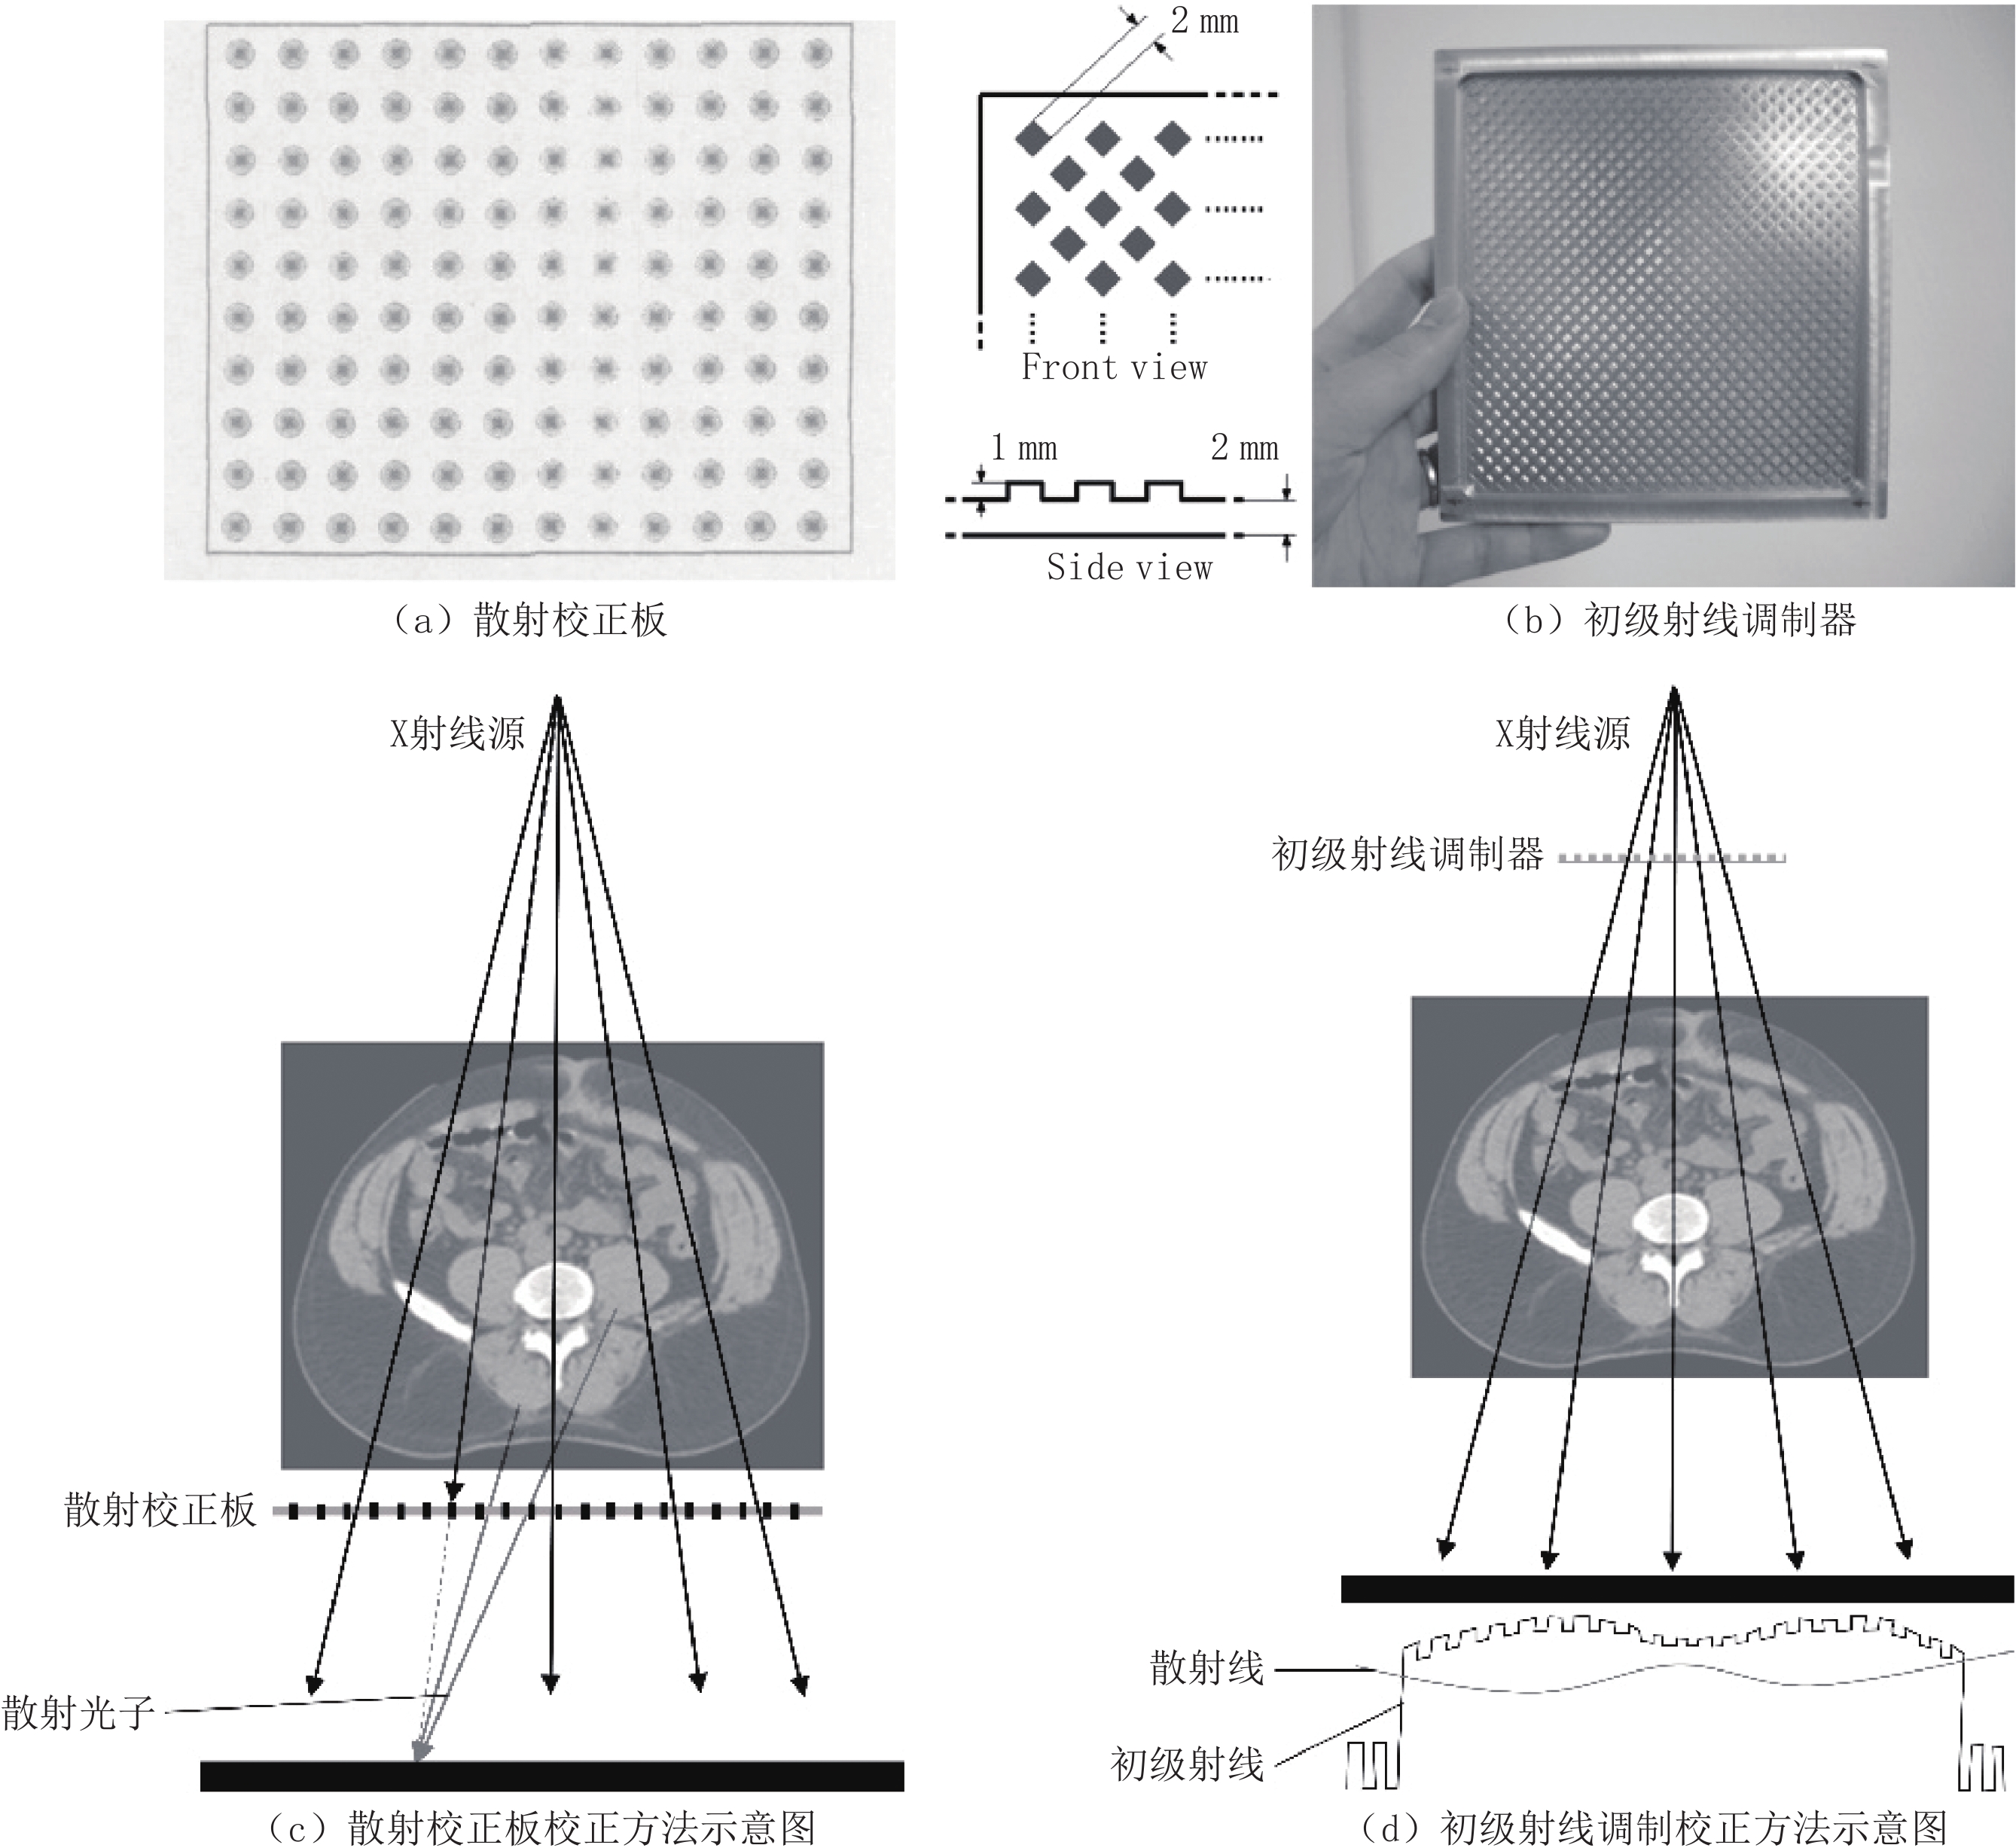

硬件校正,即在X射线成像系统的各个部件上添加一些校正工具以减少到达探测器的散射线,或者改变初始射线的能量和能谱分布[2],包括:准直器校正、反散射栅校正、滤线板校正、空气隙校正等。准直器校正是通过垂直置于探测器前的高吸收系数的薄板吸收散射线来进行校正,其结构如图1(a)所示,该方法在扇形束CT中的校正效果明显,可以去除89% 左右的散射线[9],在锥形束CT中的校正效果不明显。反散射栅校正通过置于探测器前的栅格来阻止散射线到达探测器,其结构如图1(b)所示,该方法在高X射线散射条件(大的被测物体和大的照射野)、高成像剂量和低分辨率重建,散射情况得到明显改善,在低剂量和低散射条件下,会损害图像质量,增加图像噪声,而散射也不会被很好地去除[10-11];也有学者研究移除反散射栅带来的网格伪影来提高校正图像质量[12]。滤线板校正则置于X射线出口处,吸收易发生散射的低能X射线,改善X射线质量,剩余的高能X射线具有较好的前向性,减少了散射[13],其结构如图1(c)所示。空气隙校正通过增加物体与探测器之间的距离,来进行散射校正,其结构如图1(d)所示,该方法受到投影放大比的限制会使得图像变模糊[14-15]。

$ {I_p} $ 与散射点扩展函数$ {h_{{\rm{PSF}}}} $ 进行卷积,再与权重函数$ {W_{(T)}} $ 相乘得到散射强度${I_s} = {W_{(T)}} \cdot {I_p} * {h_{{\rm{PSF}}}}$ [16],并通过实验来获得改进的散射点扩展函数中的相关系数以及权重函数,该方法非常依赖所设置的实验条件,不能提供所有可能的CT场景且完全正确的散射估计[16-18]。MC方法是随着计算机计算能力的发展而出现的以概率统计理论为指导的一类数值计算方法,该方法能够精确地模拟粒子运输,被认为是锥形束CT散射伪影校正的金标准[19],但真实模拟实际的物理过程,导致其计算量大,模拟速度缓慢[20];有许多学者也研究了MC方法的加速策略,如使用GPU加速计算过程,使用低光子数的MC仿真[21],使用深度学习方法得到低光子数到高光子数的图像映射[22],减少对未到达探测器粒子的追踪[23];使用MC和卷积核混合方法[24]等。玻尔兹曼运输方程散射估计方法首先将CT投影过程划分为3个步骤:射线源到扫描对象的光子追踪、光子在扫描对象内的吸收或散射、扫描对象中所有体素到每个探测器像素的散射通量追踪,然后使用线性玻尔兹曼输运方程确定性求解器计算每个步骤中的光子和散射光子的路径,并得到探测器处的散射光子分布,有研究表明该方法可以在临床可接受的时间内获得可靠的校正精度,是一种很有潜力的MC替代方法[25-26]。软硬件混合校正的方法包括:散射校正板校正方法、初级射线调制校正方法等。散射校正板将一块嵌有规则排列的柱状金属的有机玻璃板,置于被测物体和探测器之间[27],得到被金属阻挡位置上的散射情况,拟合得到整个散射分布,其硬件结构如图2(a)所示,校正原理如图2(c)所示,该方法需要被照射对象接受两次照射,增加患者的辐射剂量[28]。初级射线调制校正方法[29-30]将一片均匀布满突起的铝板或铜板,置于射线源和被测物体之间,形成不同的空间衰减,利用散射线的低频特性,使用高通滤波器对投影滤波,扣除散射线,得到校正后的图像[31],其硬件结构如图2(b)所示,校正原理如图2(d)所示。还有学者提出一种时域初级射线调制校正方法,使用可移动的初级射线调制器来去除伪影[32]。